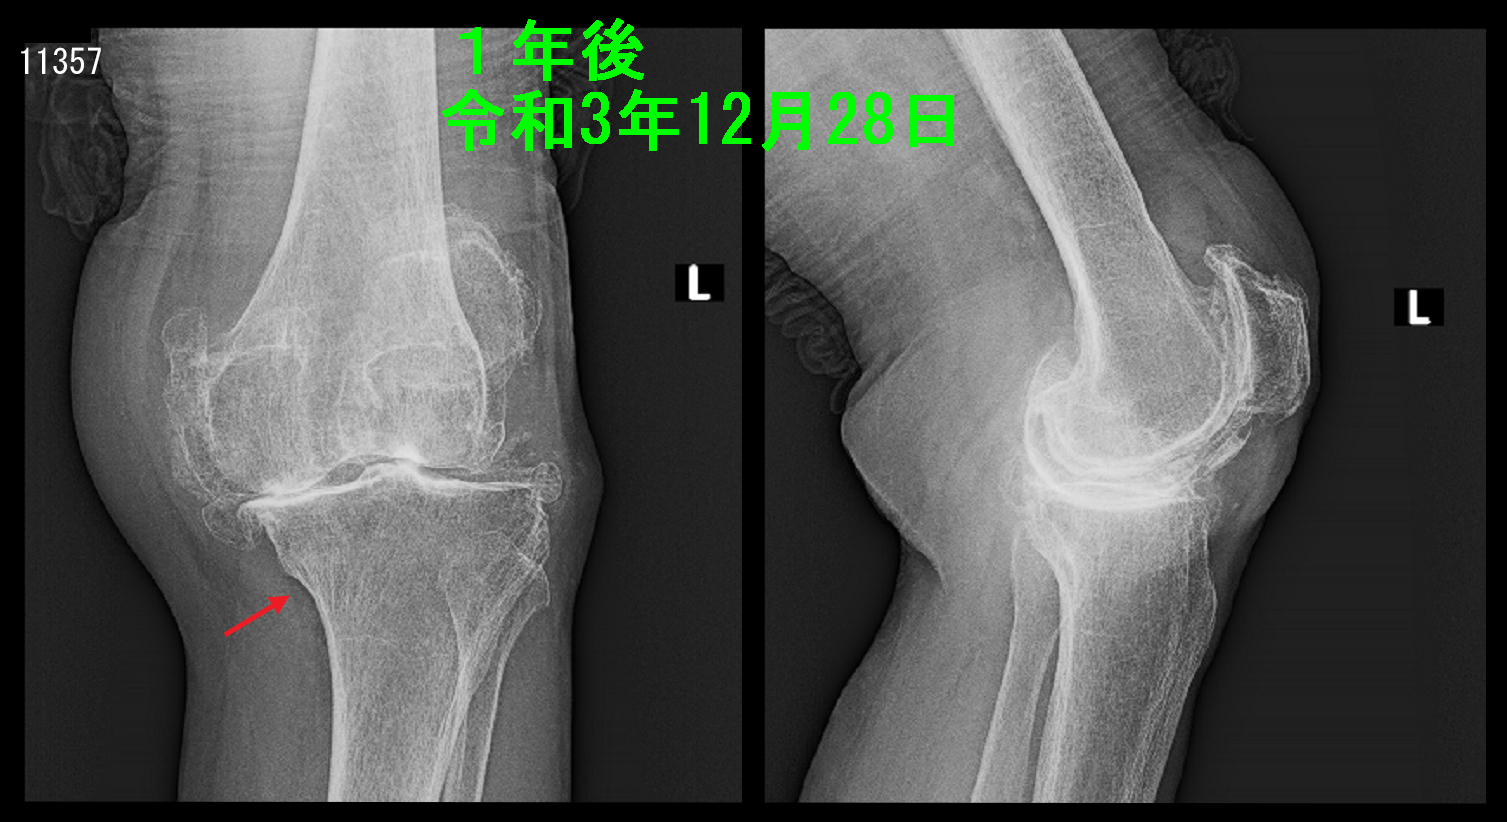

次のレントゲン像は同年の年末12月28日に10日前からの左膝痛が増悪した時の者をです。リハ退院時に確認されたしっかりとした仮骨はまったく確認できません。これはどういうことなのでしょうか。

84才 1年後Xp.jpg

私の理解は、リハビリで入院時は本人の意向はどうであったか?ですが、退院して直ぐ一人暮らしが可能となるように積極的な歩行訓練が繰り返されたのだと思います。高齢により特に怪我をしたわけでもなく(電車での立ち上がりの動作だけで)骨の損傷を発症した弱い骨粗鬆症の骨は十分に骨が丈夫になっていないのにもかかわらず、積極的に歩行訓練を強制されることにより、その歩行の負荷は骨を壊す負荷として働いていたと思われます。そのため歩行訓練の負荷に負けないように骨折した脛骨は必要以上に仮骨を生成して歩行訓練に耐えられる骨の状態を構築していたと思われます。しかし、退院した後は83才の女性は一人暮らしで積極的に歩行訓練をするはずもなく、痛くない程度に必要最低限度の移動で生活をしていたはずです。そうなると骨折部に働いていた体重負担はぐっと軽減したため、過剰な仮骨は必要なくなったのです。それを体が感知して、過剰に生成された仮骨を吸収していったと考えられます。

このように(高齢になっても)人体は人間にとって必要最小限度の修復(骨形成)しか行わないようにできているのです。